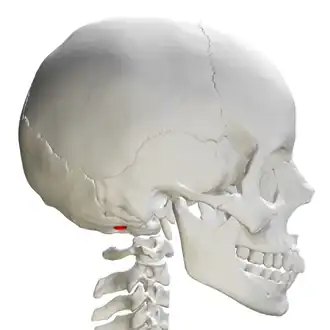

![]() Skull and cervical vertebra. Position of condyloid fossa shown in red. | |

Behind either condyle of the lateral parts of occipital bone is a depression, the condyloid fossa (or condylar fossa), which receives the posterior margin of the superior facet of the atlas when the head is bent backward; the floor of this fossa is sometimes perforated by the condyloid canal, through which an emissary vein passes from the transverse sinus.

Skull and cervical vertebra. Position of condyloid fossa shown in red. -